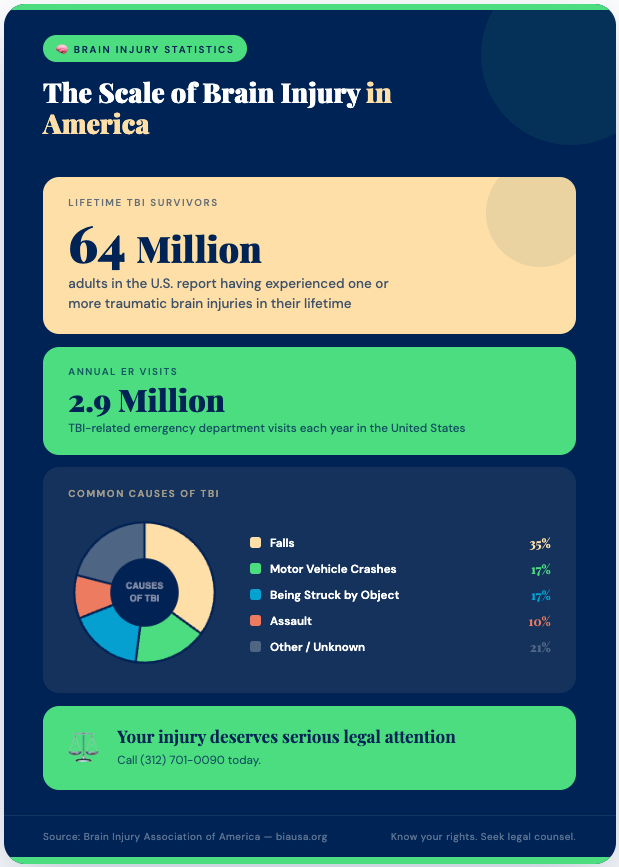

Brain Injury Statistics

According to the Brain Injury Association of America, at least 64 million adults report having experienced one or more TBIs in their lifetime, and there are 2.9 million TBI-related emergency department visits each year in the United States alone. If you or a loved one suffered a brain injury due to someone else’s negligence in Chicago, you may be entitled to significant compensation — and an experienced attorney can help you fight for it.